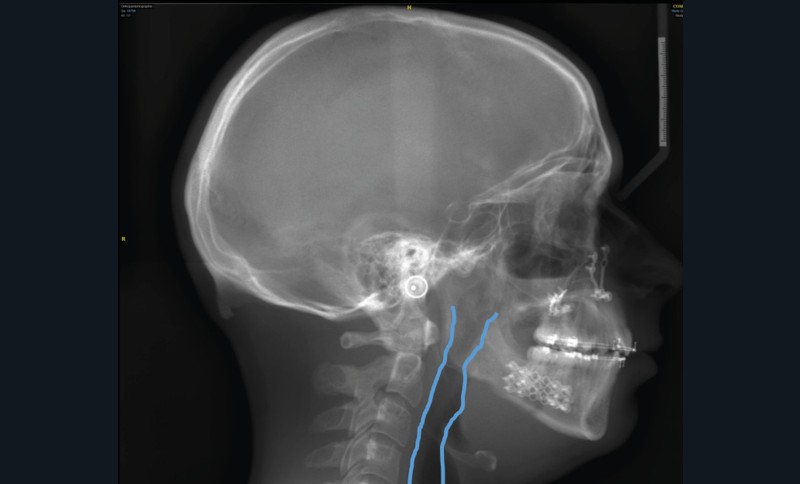

C’est à ces questions que nous permettront de répondre les deux premiers conférenciers, parodontologistes : le Dr Béatrice Straub nous présentera le renfort parodontal minéralisé, technique qu’elle a développée et pratique depuis de nombreuses années, pour éviter les préjudices des mouvements orthodontiques à risque, notamment lors des décompensations préchirurgicales (fig. 1a-d) ; le Pr Anton Sculean abordera le thème des greffes, avec leurs indications, les différentes techniques à privilégier et illustrera ses propos par de nombreux cas cliniques aux résultats esthétiques impressionnants.

Le Dr François Cheynet et à nouveau le Pr Michel Le Gall (fig. 12) viendront plaider pour une prise en charge chirurgicale précoce de certains décalages squelettiques, afin de briser au plus vite la spirale dysmorpho-dysfonctionnelle et influencer le schéma de croissance postopératoire.